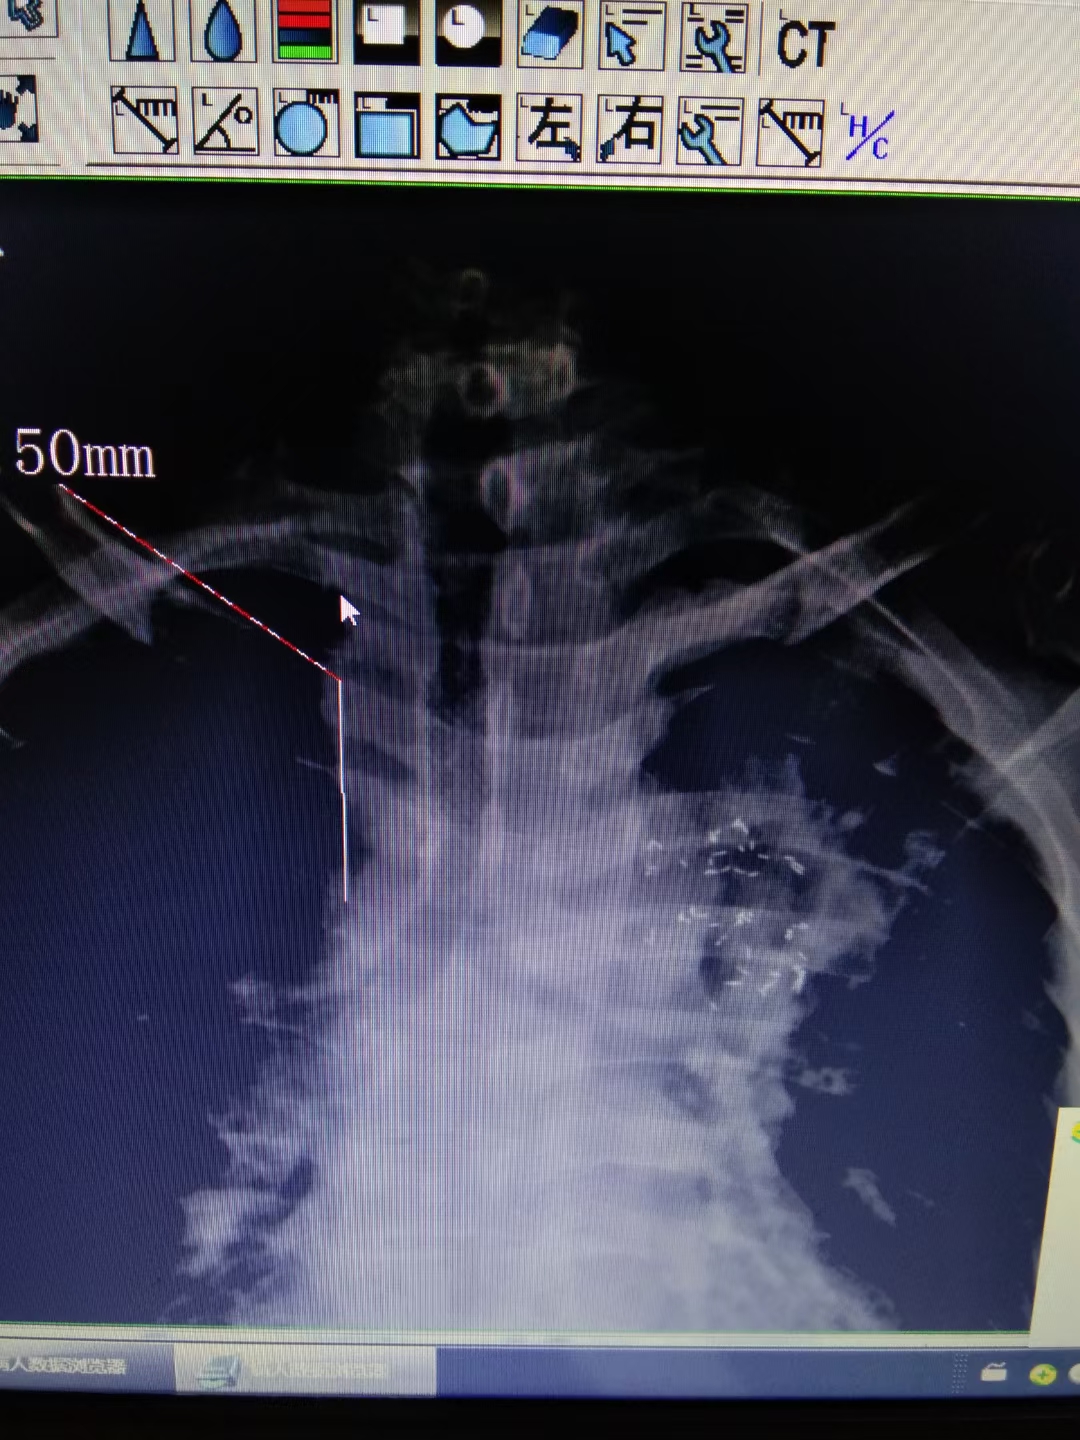

病例1

一般肿瘤压迫气管,不适合手术的情况下,可以放置气管支架,维持气管的通畅,保证呼吸功能。维持患者的生命。